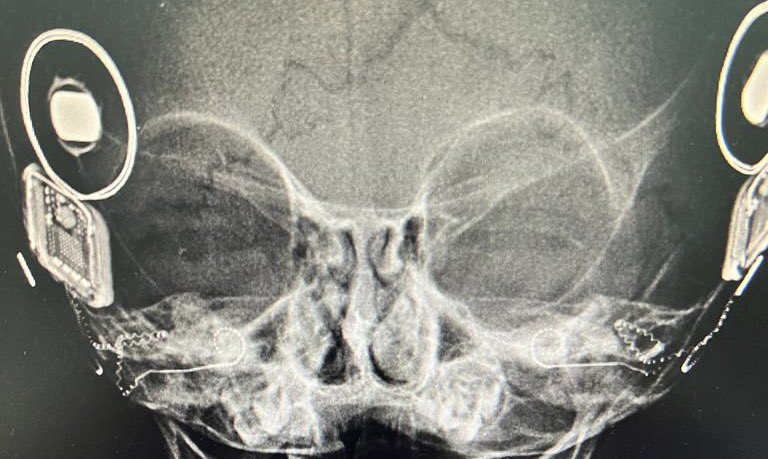

زراعة القوقعة بين الماضي والحاضر

#زراعة_القوقعة